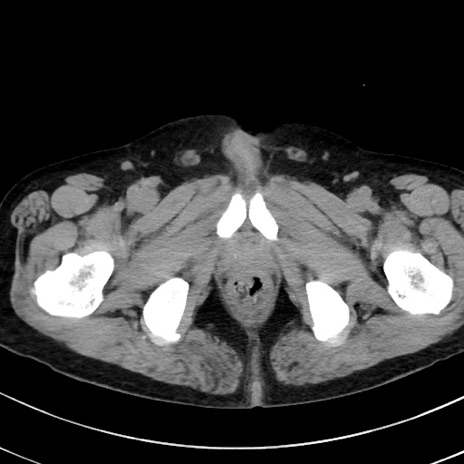

症例38(横断像)

【症例】70歳代 男性

【主訴】腹痛・嘔吐

【現病歴】昨晩より、嘔吐・腹痛あり。今朝になっても嘔吐あり。来院。

【既往歴】心臓バイパス手術、開腹胆摘、腸閉塞

【身体所見】BP 107/71mmHg、HR 116/min、腹部:平坦、軟、下腹部に軽度圧痛あり。反跳痛なし。

【データ】WBC 15100、CRP 0.32